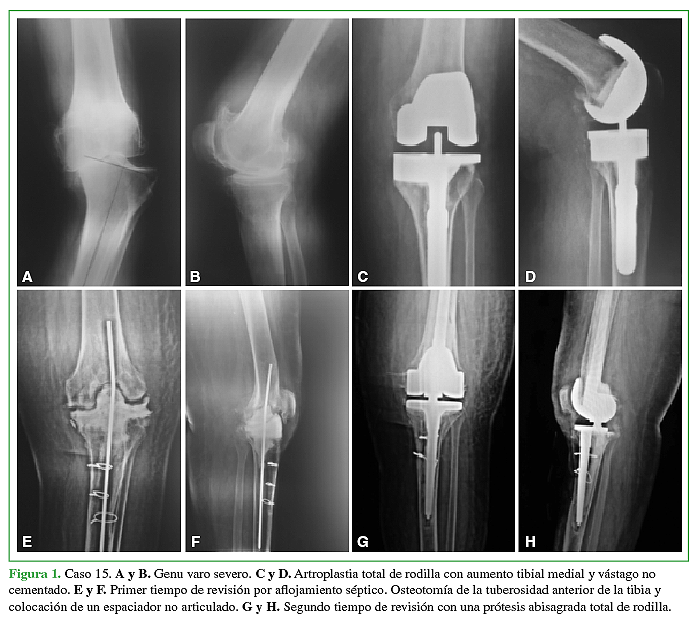

El seguimiento promedio fue de 6.5 años (rango de 2 a 12 años). El rango de movilidad conseguido fue 110º de flexión (rango de 70º – 130º) y 5º de extensión (rango de 0º a 20º). El puntaje promedio en el KSS mejoró de 38 en el preoperatorio a 82 en el postoperatorio. En la evaluación radiológica detectamos en 8 (23%) casos líneas radiolúcidas > a 2mm alrededor del componente femoral y/o tibial o alrededor de los vástagos. Cinco de 34 prótesis (14.7%) presentaron complicaciones. En 3 casos (8.9%) se trató de una infección profunda. Dos casos (5.9%) presentaron complicaciones patelo-femorales. La sobrevida de la prótesis libre de revisión a los 6.5 años fue de 94%. Si consideramos el aflojamiento aséptico como causa de revisión la sobrevida fue del 100%.